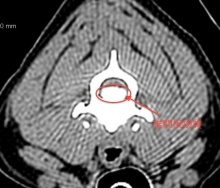

横の画像が正常の頸椎のCT画像です。下の写真に比べてもらうと、脊髄神経がはっきり見えるのがよく分かると思います。

次に、横の画像がリリーちゃんの圧迫を受けている頸椎のCT画像です。上の写真に比べると、下側から、大量の椎間板物質に圧迫されているのがよくわかりますよね。